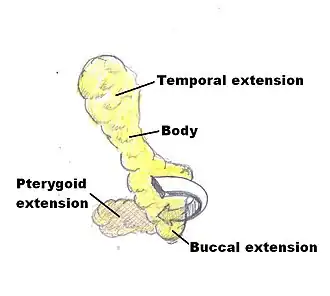

Cheek reduction: Anatomic illustration of the fat pads of the mouth (buccal fat pads).

Cheek reduction: Anatomic illustration of the fat pads of the mouth (buccal fat pads). -